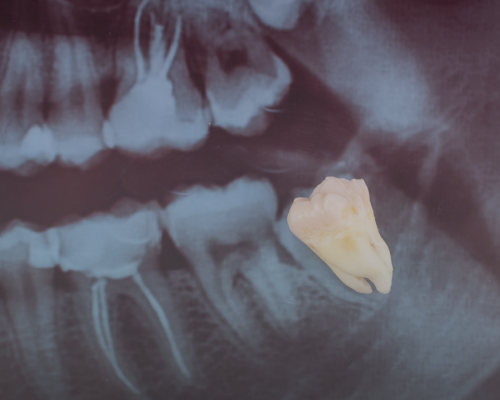

Wisdom Tooth Extraction

• Impacted teeth tackled: No wisdom tooth is too tricky – our experts handle even complex removals with confidence.